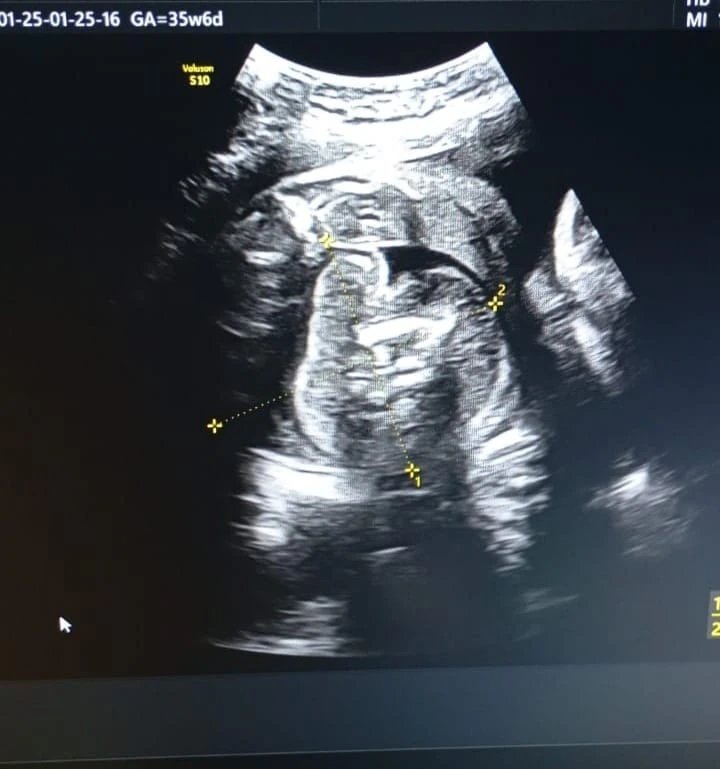

In Buldhana, Maharashtra, a very uncommon medical occurrence occurred when a baby was found within the womb of an unborn kid. Two days ago, when a 32-year-old lady had a sonography, a case of "foetus-in-fetu" was discovered at a government hospital. just 200 examples of this uncommon congenital defect have been reported globally, with just 15 to 20 of those occurrences occurring in India.

Gynecologist Dr. prasad Agarwal, who found the non-developing fetus, stated, "I was initially surprised and then carefully re-examined the images." He went on to say, "It was a case of a foetus-in-fetu."

Due to its extraordinary rare and unpredictable nature, this aberration was missed in previous examinations, and the woman was in her ninth month of pregnancy.

Since this is a very uncommon ailment, no one can even fathom that it may exist, which is why the earlier sonography missed it. Thus, I conducted a thorough investigation with a few medical professionals and verified it," Dr. Agarwal stated.